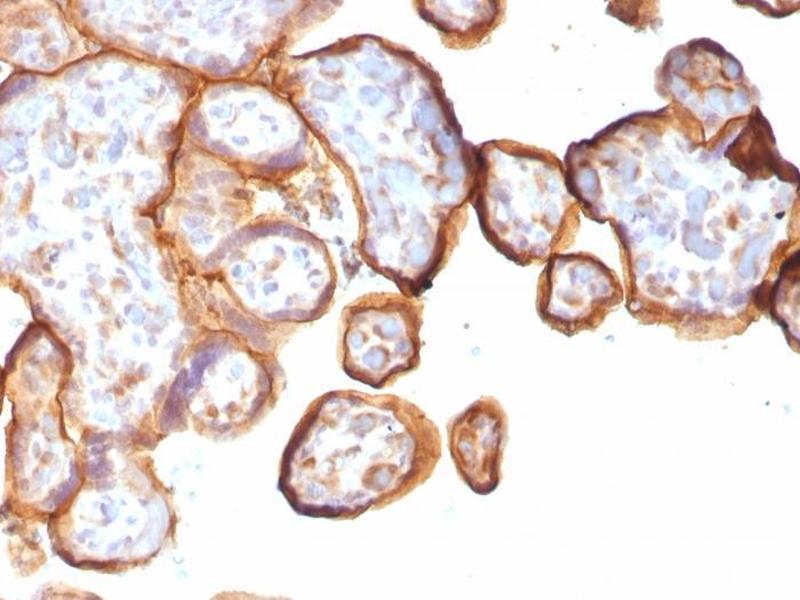

Thrombomodulin 抗体

(Thrombomodulin (THBD))

The protein encoded by this intronless gene is an endothelial-specific type I membrane receptor that binds thrombin. This binding results in the activation of protein C, which degrades clotting factors Va and VIIIa and reduces the amount of thrombin generated. Mutations in this gene are a cause of thromboembolic disease, also known as inherited thrombophilia. [provided by RefSeq, Jul 2008].